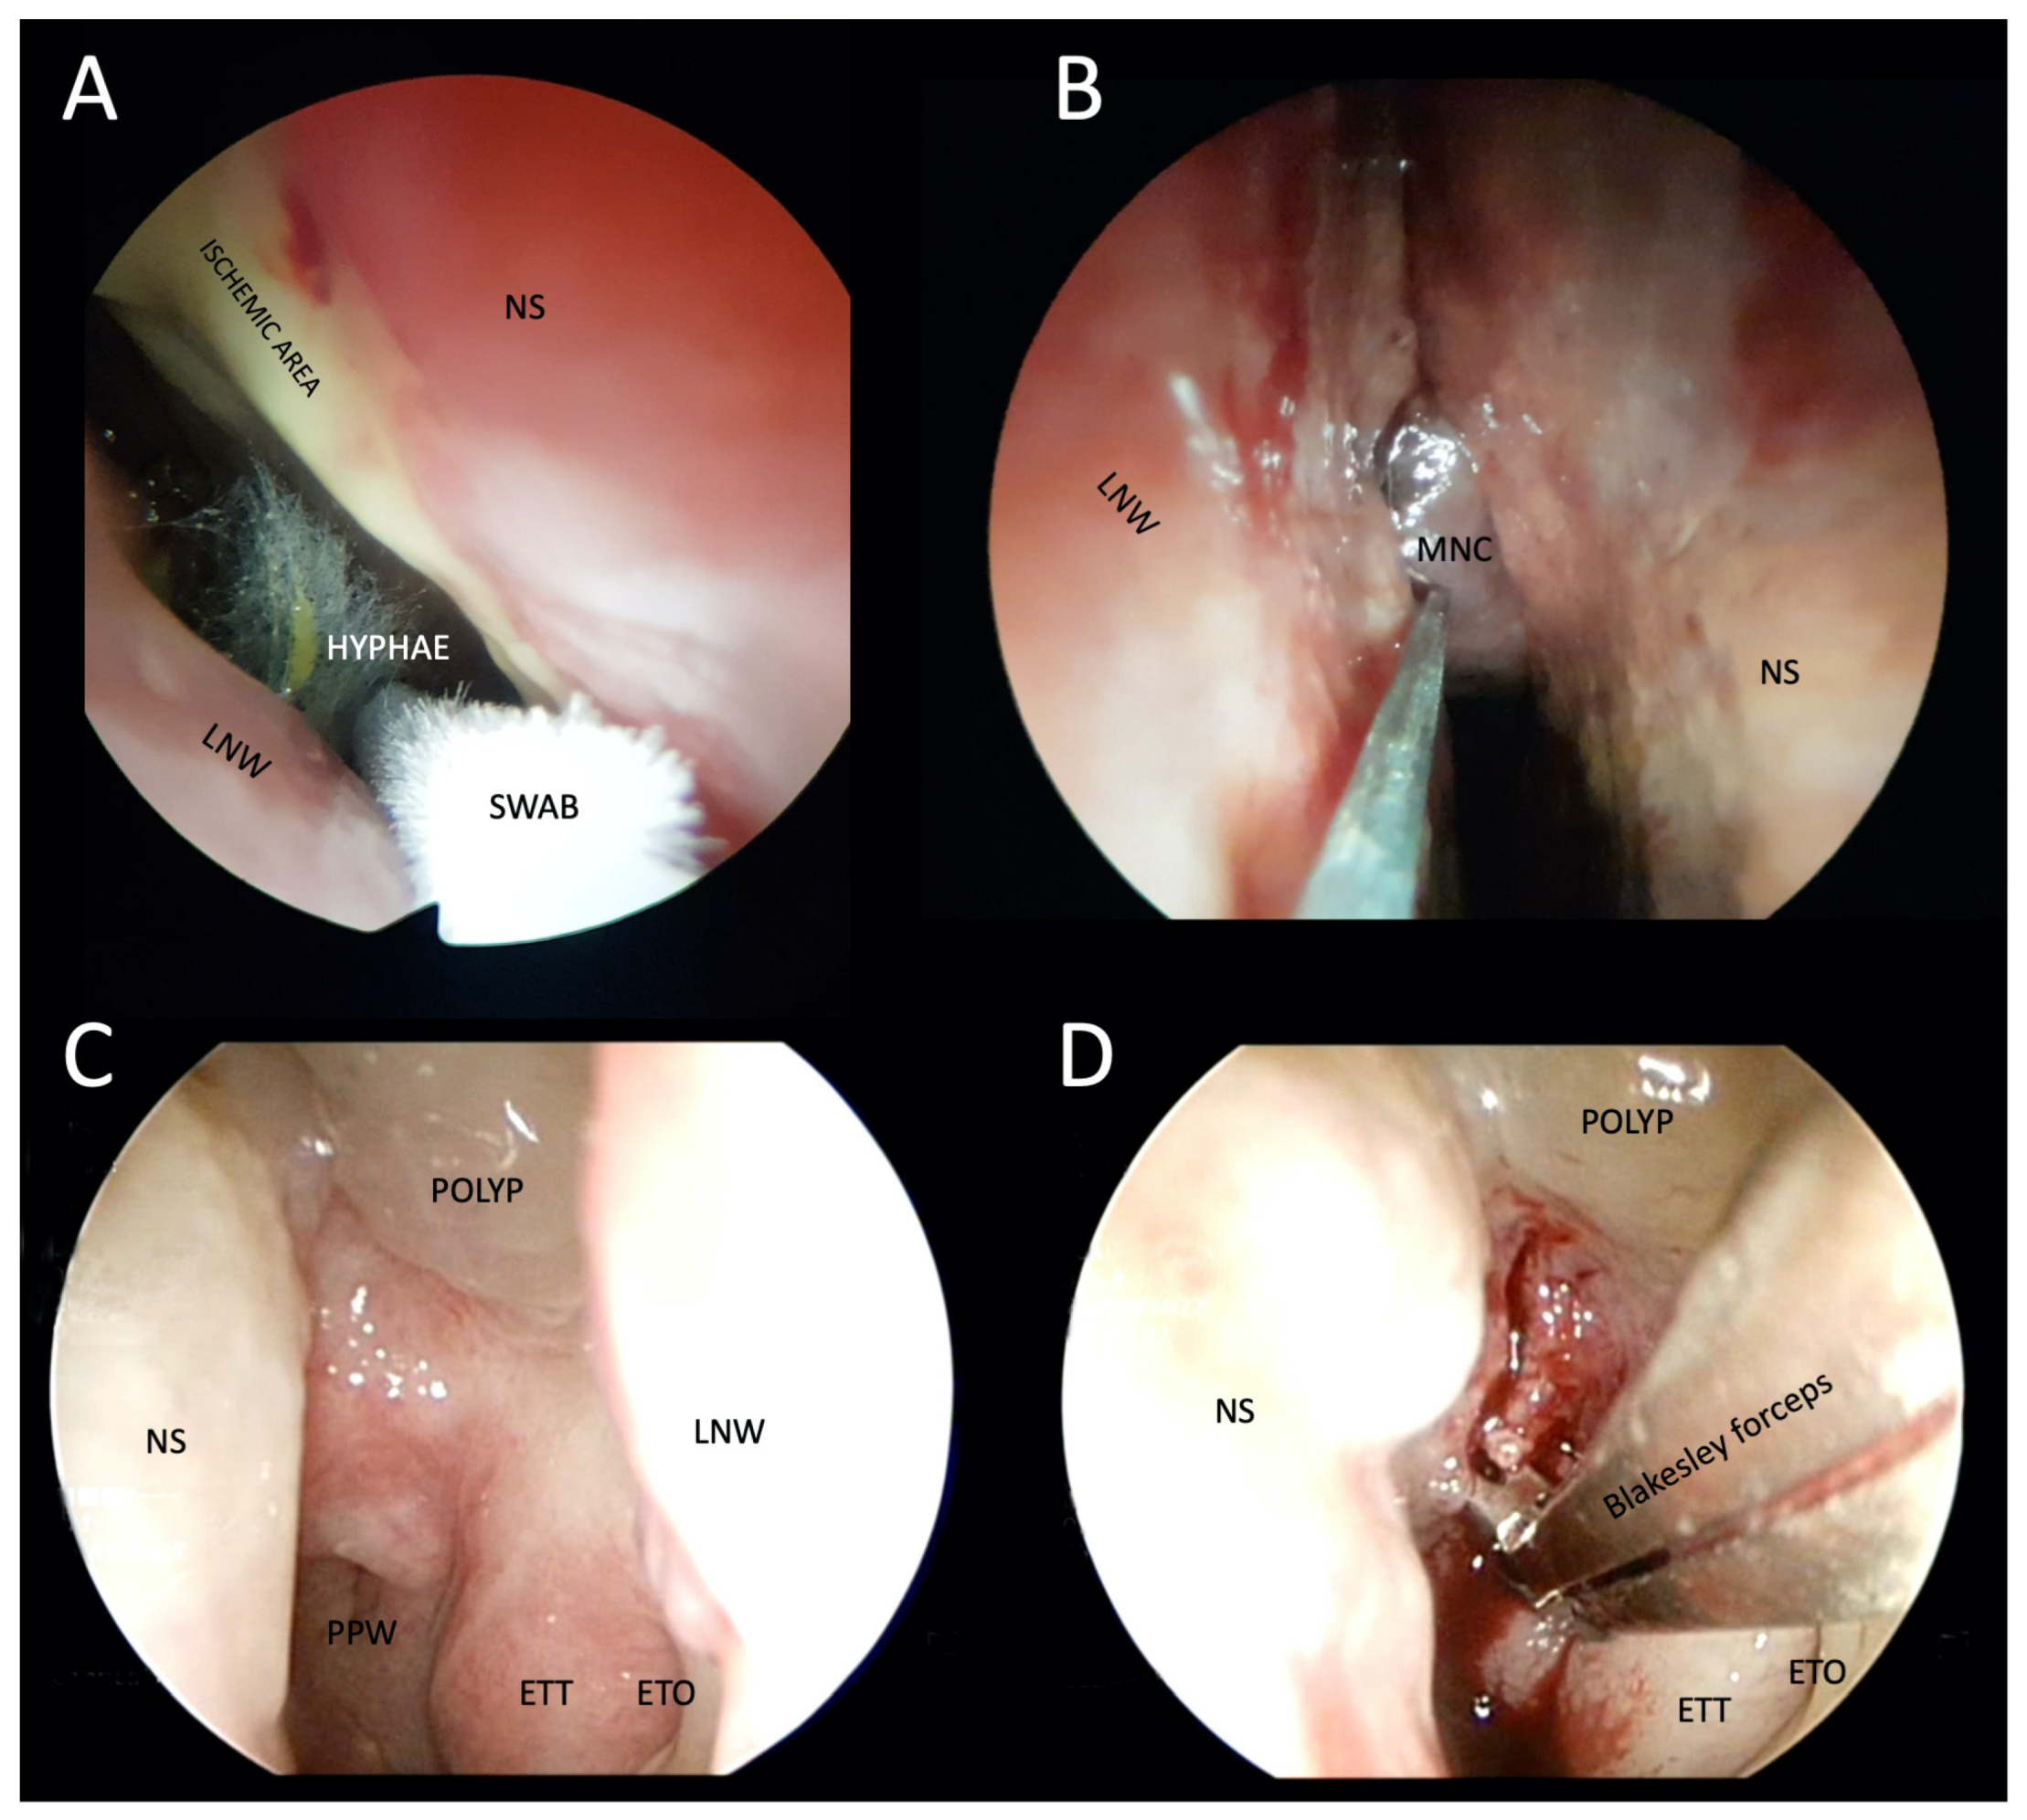

4.2. Otorhinolaryngological Examination and Tissue Specimen Sampling

4.3. Histopathology

4.4. Microbiology Studies